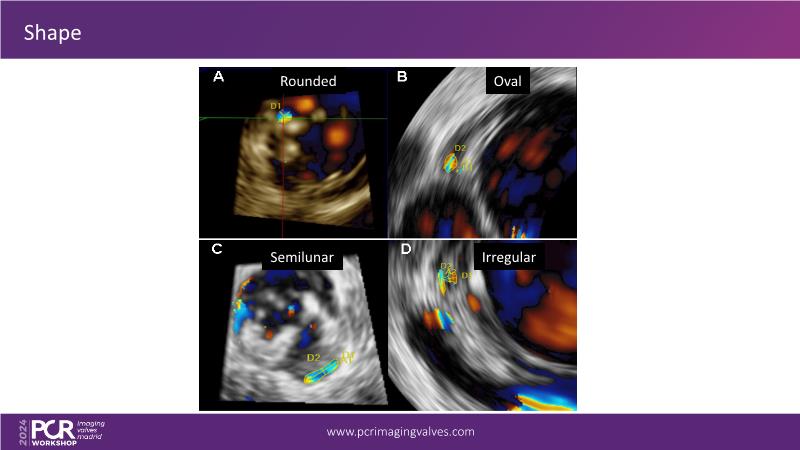

Explore cutting-edge transcatheter valve interventions for mitral and aortic valve disorders, including valve-in-valve procedures and management strategies for paravalvular leakages, and learn about diagnosing and treating mitral annular calcification and transcatheter options in infective endocarditis.

- To get tips and tricks for guidance of transcatheter intervention